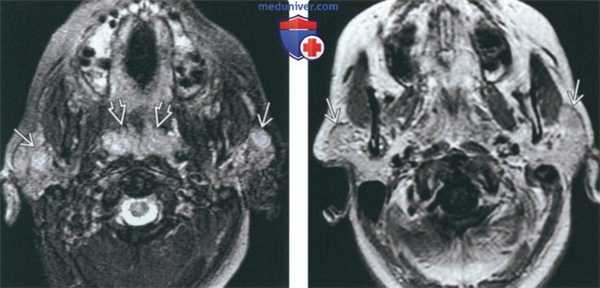

(Слева) На аксиальной MPT (Т2 FS) в обеих околоушных железах определяются объемные образования с сигналом высокой интенсивности. И солидные, и кистозные ДЛЭП характеризуются гиперинтенсивным Т2 сигналом. Обратите внимание на увеличение глоточных миндалин.

(Справа) На аксиальной МРТ (Т1 С+) визуализируются объемные образования в обеих околоушных железах с контрастирующимся «ободком». Солидные ДЛЭП сложнее выявить на исследованиях с контрастом из-за «смешивания» контрастирующихся участков с жировой тканью околоушной железы.